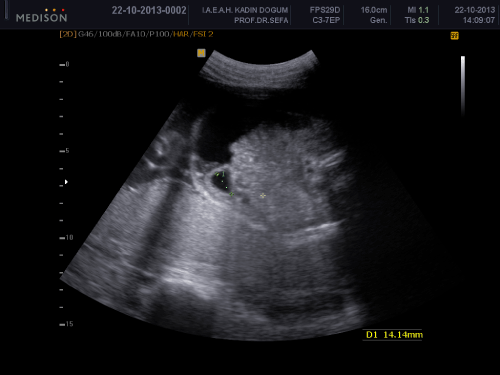

A 34-year-old woman, gravity 2, parity 0, abortion 1 is referred to our clinic at 32 weeks of gestation because of fetal intraabdominal cystic formation. She had an unremarkable prenatal course until this week. In history, she had no clinical significant coincident disease. We learned that she attended all prenatal visits regularly and she had no pathological finding in all previous visits. In the 32 weeks ultrasonography fetal biometric measurements were compatible with gestational age, amniotic fluid volume was in normal limits. Maternal blood pressure was 110/70mmHg and fetal movements were well. In ultrasonography, we detected a 15mm spheric cystic formation on the left lower side of fetal abdomen (Figure 1). The cystic formation was not related with renal structures and bladder. In Doppler sonography, we did not determine intracystic blood supply. Bilateral renal structures were evaluated normal, fetal intestines were observed normal. Because the fetus is female, cystic formation was anechoic and fetus had no accompanying genitourinary or gastrointestinal abnormalities we primarily suggested on an ovarian cyst. Due to existing fetal ovarian cyst, patient was evaluated about maternal diabetes and hypothyroidism again and resulted both in normal limits. Patient was called for a new visit two weeks later. In the 34 th week, ultrasonography fetal growth was compatible with 34 weeks gestation and amniotic fluid was in normal limits again. Only abdominal circumference was measured as 99% for this week because of fetal intraabdominal fluid. In fetal abdomen, a widespread fluid accumulation was observed (Figure 2). Ovarian cyst on the left fetal ovary was regressed and was measured 14 mm with an ellipsoid shape (Figure 3). Intestines were floating in this fluid. Fetal thorax was normal and hydrothorax was not determined. We did not observe edema in subcutaneous tissue and we evaluated as primary fetal ascites even so we performed an assessment about hydrops fetalis. Hemogram, HbA1c, VDRL, TORCH screening, Parvovirus B-19 screening, indirect coombs test and anticardiolipin IgM and IgG studies were performed. Middle cerebral artery peak systolic velcity was 55cm/sec(1,12 MOM) and was not signifying fetal anemia. We recommended fetal karyotyping to patient because it could be an onset of fetal hydrops. However, patient did not accept karyotyping. All screenings were evaluated normal. Fetal cardiac examination was normal. Patient was called for a visit two weeks later again. At the next examination in the 36th weeks of pregnancy, fetal ultrasonography was completely normal. We have not observed any fetal ovarian cyst and fluid in fetal abdomen was completely regressed. Patient had a 3400 gr healthy baby on the 40th weeks of her pregnancy. No abnormal finding determined in postnatal abdominal ultrasonography.

Figure 3: 14mm regressed ovarian cyst on the left fetal ovary.